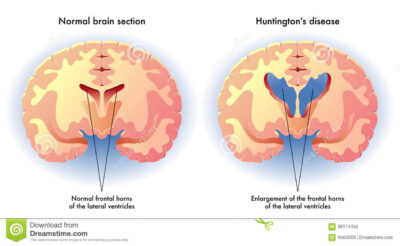

La malattia di Huntington è una malattia neurodegenerativa genetica fatale che provoca la progressiva rottura delle cellule nervose nel cervello. Si stima che circa 250.000 persone negli Stati Uniti siano diagnosticate o a rischio per la malattia. I sintomi includono cambiamenti di personalità, sbalzi d’umore e depressione, dimenticanza e capacità di giudizio alterate, andatura instabile e movimenti involontari. Ogni figlio di un genitore MH ha una probabilità del 50% di ereditare il gene. I pazienti in genere sopravvivono 10-20 anni dopo la diagnosi.